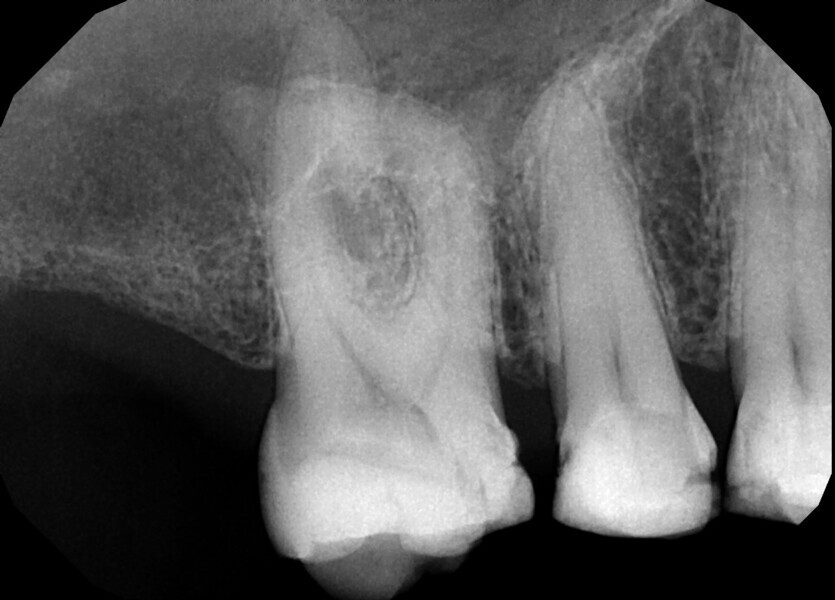

Fig. 17a: Case assisted with CBCT to determine anatomy pre-operatively. Note the multiple cross sections moving apically and the correlation to the 2-D view. Note also the conservative taper in relation to the root width. (Courtesy of Dr. Brett Gilbert)

Fig. 17b: Case assisted with CBCT to determine anatomy pre-operatively. Note the multiple cross sections moving apically and the correlation to the 2-D view. Note also the conservative taper in relation to the root width. (Courtesy of Dr. Brett Gilbert)

Fig. 17c: Case assisted with CBCT to determine anatomy pre-operatively. Note the multiple cross sections moving apically and the correlation to the 2-D view. Note also the conservative taper in relation to the root width. (Courtesy of Dr. Brett Gilbert)

Fig. 17d: Case assisted with CBCT to determine anatomy pre-operatively. Note the multiple cross sections moving apically and the correlation to the 2-D view. Note also the conservative taper in relation to the root width. (Courtesy of Dr. Brett Gilbert)

Fig. 17e: Case assisted with CBCT to determine anatomy pre-operatively. Note the multiple cross sections moving apically and the correlation to the 2-D view. Note also the conservative taper in relation to the root width. (Courtesy of Dr. Brett Gilbert)

Fig. 17f: Case assisted with CBCT to determine anatomy pre-operatively. Note the multiple cross sections moving apically and the correlation to the 2-D view. Note also the conservative taper in relation to the root width. (Courtesy of Dr. Brett Gilbert)